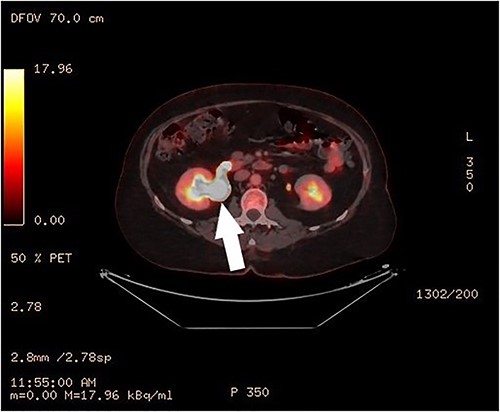

Clinical vaginal examination revealed a circumferentially distended uterine cervix. Vaginal ultrasound scan and magnetic resonance imaging (MRI) showed a strongly vascularized mass that completely involved the whole cervix. The mass measured 118 × 117 × 124 mm and showed irregular echogenicity with signs of diffuse necrosis centrally, suspicious for sarcomatous degeneration (Fig. 1). Positron emission tomography-computed tomography (PET-CT) showed a heterogenous and irregular hypermetabolic uterus, suspected for malignancy (Fig. 2). There were no signs of distant metastases nor lymphadenopathy. PET-CT also showed a distended ureter with hydroureteronephrosis on the right side, suspicious of compression/obstruction of the right ureter (Figs 2–4).

PET-CT, coronal image of a dilated right ureter with stenosis at the pelvic mass.